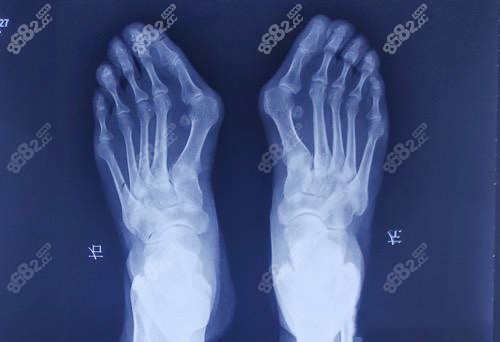

讓蘇醫(yī)生或者他的團(tuán)隊醫(yī)生親眼看看你的腳,拍個X光片,測量一下具體角度,才能給出較比較準(zhǔn)的價格和較適合你的手術(shù)方案。

看真實實例:多去搜搜蘇敬達(dá)醫(yī)生的真實實例,特別是和你腳型類似的,這樣你對術(shù)后結(jié)果會有一個更現(xiàn)實的預(yù)期。